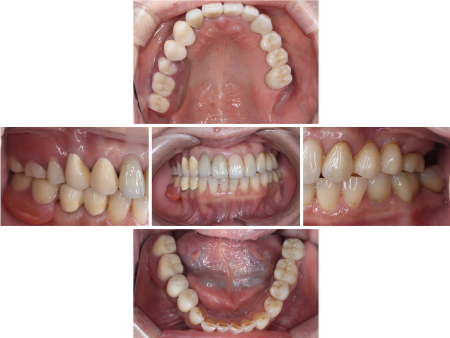

拝見したところ、上の奥歯6本(左第1小臼歯/4番、左右第2小臼歯/5番、右第1大臼歯/6番、左右第2大臼歯/7番)と右下の奥歯2本(第1大臼歯、第2大臼歯)が欠損しており、その部分を補うために装着されていた義歯が劣化している状態でした。

被せ物が装着されている歯のうち、左下の奥歯3本(第2小臼歯、第1大臼歯、第2大臼歯)と右上の前歯2本(中切歯/1番、側切歯/2番)は、過去に歯の神経が入っている管をきれいにして薬剤を詰める「根管治療」が行われており、右上の奥歯(第1小臼歯)と左上の前歯(犬歯/3番)、左上の奥歯(第1大臼歯)の3本は神経が残っていたものの、計6本については神経が炎症を起こしている状態でした。

左下の奥歯3本(第2小臼歯、第1大臼歯、第2大臼歯)は、被せ物を取り除いてから再度根管治療を行い、ジルコニアクラウンを作製し装着しています。

左上の前歯(犬歯)と左上の奥歯(第1大臼歯)は被せ物を外し根管治療を行ったあと、欠損している奥歯2本(第1小臼歯、第2小臼歯)を補うジルコニアブリッジの土台として形を整え、4本つなげて装着しました。

右上の第1小臼歯と右上の犬歯は劣化した被せ物を取り除き、第1小臼歯の根管治療をしてから、それぞれ右上用のコーヌス義歯の土台歯として形を整えています。

同様に、右下の第1小臼歯と第2小臼歯も右下用のコーヌス義歯の土台歯として形を調整し、右上下それぞれの土台歯に金属の被せ物を入れて、その上から入れ歯を装着しました。

コーヌス義歯を装着後、再度歯科専門医がお口全体を確認したところ、右上の前歯2本(中切歯、側切歯)も再根管治療が必要であることがわかり、患者様に事情を説明し同意をいただいた上で、被せ物の除去と再根管治療を行ったあとジルコニアクランで修復し、治療を終了しました。